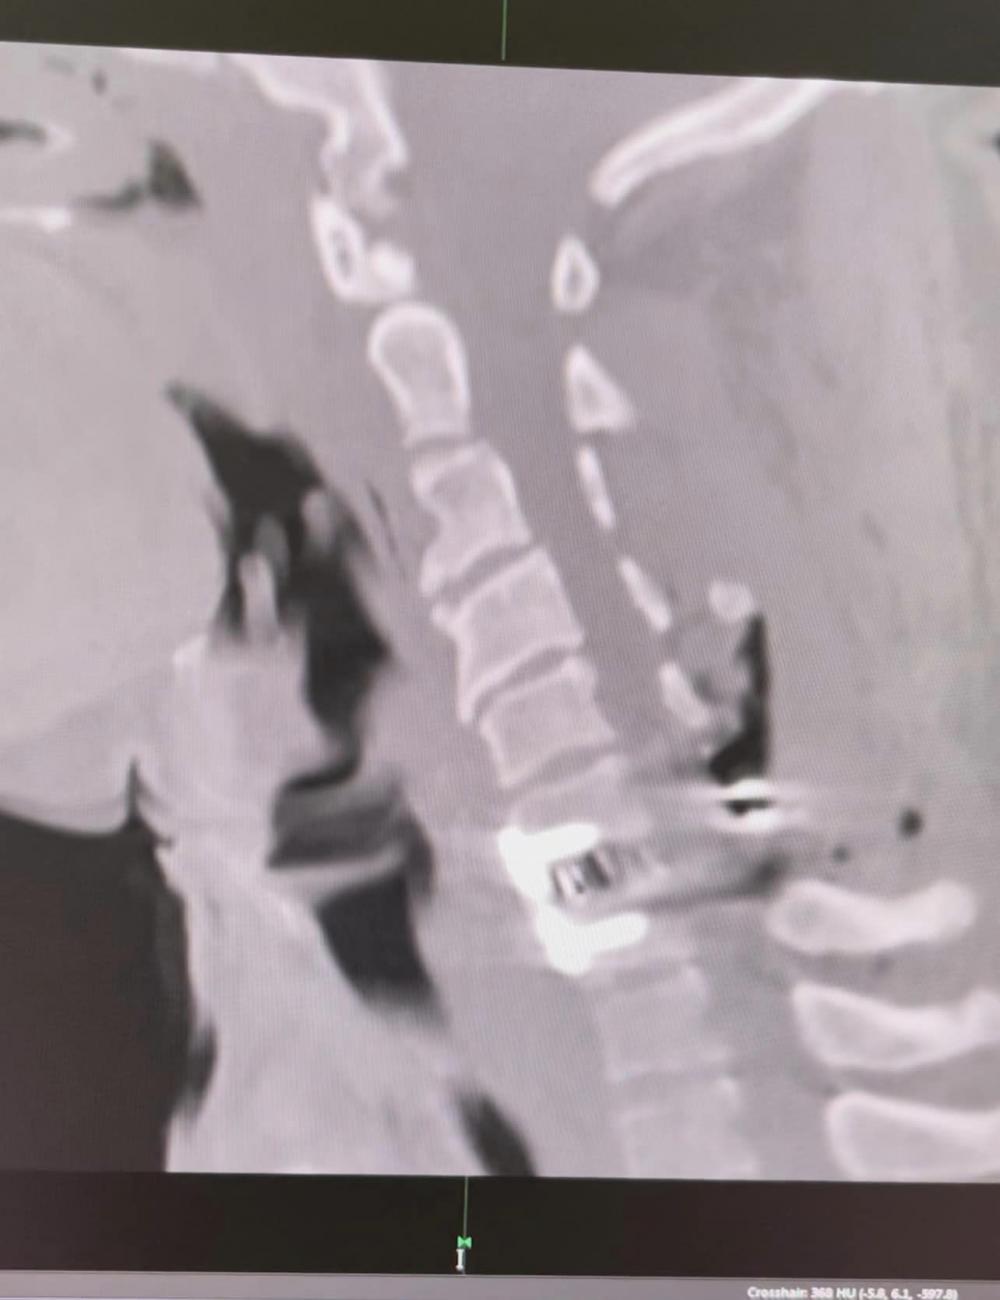

За словами медика, постраждалому було проведено КТ шийного відділу хребата та діагностовано ускладнену хребетно-спінальну травму.

Тому прийняли рішення про проведення операції-стабілізації 360 градусів переломовививиху С6-С7.

"Перший етап полягав в усунення вивиху та проведення задньої стабілізації. Під час другого - провели передній корпородез. Пацієнта перевернули на спину, виконали передню дискектомію С6-С7, встановили кейдж на рівні С6-С7 та зафіксували передньою пластиною гвинти (15мм,) імплантовані у тіла С6-С7", - розповів нейрохірург.